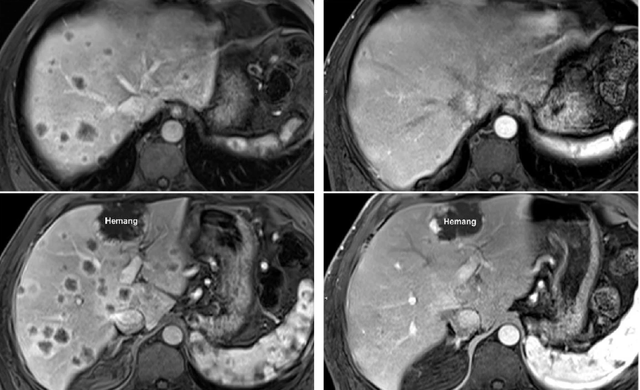

肝癌:早期临床显示100%患者存活,80%无疾病证据

我国中山大学肿瘤中心曾经开展的一项自体肿瘤浸润淋巴细胞(TIL)针对原发性肝细胞癌(HCC)患者的I期临床试验中,经过14个月的随访,15例(100%)的患者全部存活,12例患者(80%)无疾病证据。这些数据表明,输注自体TIL在该患者群体中是可行的。